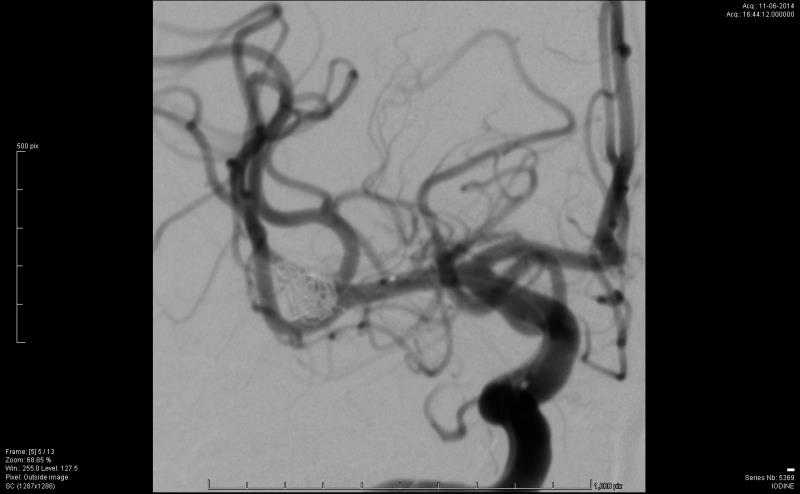

Άντρας ασθενής 55 ετών, νοσηλεύτηκε λόγω υπαραχνοειδούς αιμορραγίας και διαγνώσθηκε με ρήξη ανευρύσματος μέσης εγκεφαλικής αρτηρίας. Υποβλήθηκε σε ενδαγγειακή αντιμετώπιση με coils (εμβολισμός) και έλαβε εξιτήριο μετά την ολοκλήρωση της αγωγής του.

Πέντε μήνες αργότερα και παρά την ικανοποιητική αγγειογραφική εικόνα τόσο κατά τον εμβολισμό όσο και κατά τον επανέλεγχο στο μεσοδιάστημα, διαγνώσθηκε με νέα ρήξη του ίδιου ανευρύσματος, ενώ ο αγγειογραφικός έλεγχος κατέδειξε compaction των coil.

Στις προεγχειρητικές φωτογραφίες απεικονίζονται κατά σειρά ο αρχικός εμβολισμός, η εικόνα της επαναιμορραγίας σε αξονική τομογραφία και ο αγγειογραφικός έλεγχος μετά την επαναιμορραγία.